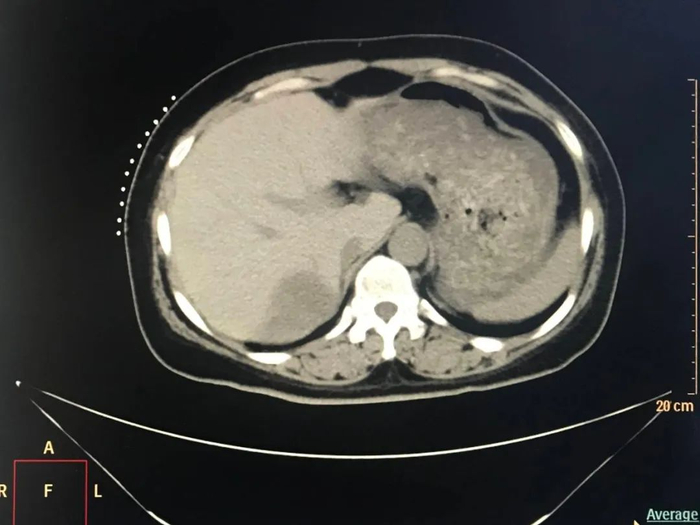

2023年4月,患者复查肝脏MRI显示病灶较前(2023年2月)增大。为了进一步控制患者病情,邢台市第九医院肿瘤内科一区团队会诊后,决定对她实施放射性粒子植入治疗。2023年5月,患者接受了CT引导下肝恶性肿瘤放射性粒子植入治疗,术后恢复良好。

放射性粒子植入术属于近程放疗,通常在超声或CT引导下进行,主要将125I粒子由细针直接穿刺至肿瘤并植入内部,通过其放射特性摧毁肿瘤。其优点在于125I粒子的射程较短、局部剂量高,便于把射线控制在肿瘤灶内,从而减少了射线对正常组织的损伤[1]